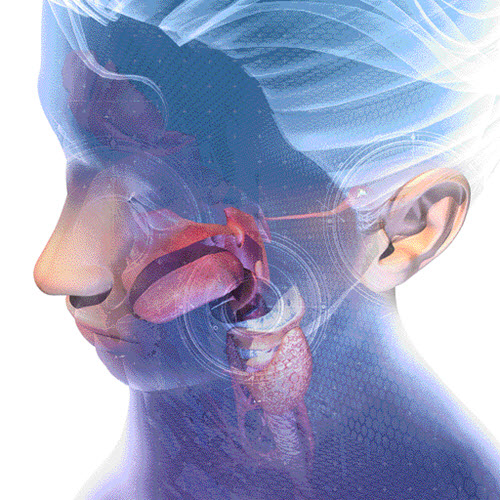

Mouth And Throat Cancer - Ear, Nose, And Throat Disorders - MSD Manual

ear throat cancer mouth nose symptoms manual loss hearing sudden disorders

Mouth and throat cancer. Ear throat cancer mouth nose symptoms manual loss hearing sudden disorders. Trachoma trachomatous follicular determinants prevalence antibiotic lowers glossary